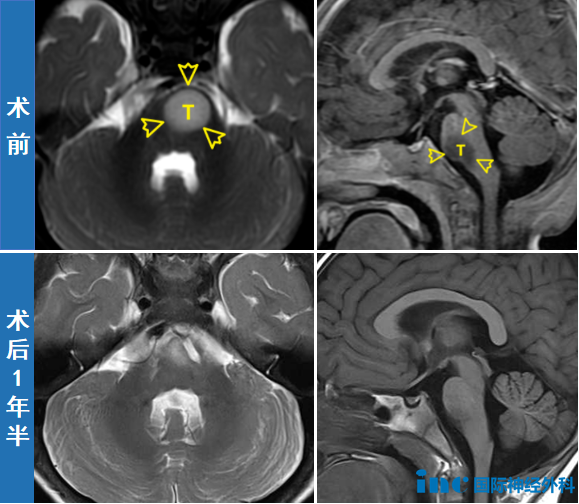

然而,最终这台让不少人望而却步的高难度开颅手术顺利完成。11个月大时,安安成功接受了手术。术后恢复良好,能和父母一起玩游戏,在病床上蹦蹦跳跳。术后一年半,已经两岁多的安安和普通孩子一样,喊出了第一声"妈妈""爸爸",迈出了第一步,学会了第一支舞——这些人生中珍贵的时刻,家人一个都没有错过。